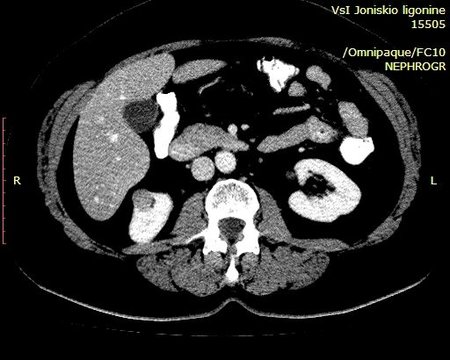

Выполнена КТ с контрастированием.

Гистология - ангиомиолипома (выполнена резекция опухоли).